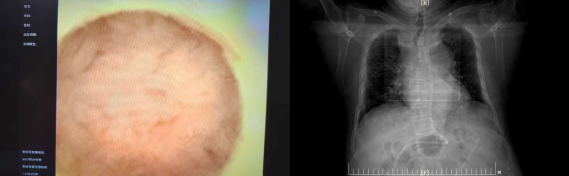

此次我院引进的床旁便携式可视化引导下鼻肠管置入技术,核心优势在于置管全程可视化。操作者通过高清内窥镜,可实时清晰观察食管、胃、十二指肠的解剖结构,如同为置管操作装上“透视眼”,精准把控导管走向,一次性将鼻肠管送达十二指肠或空肠的目标位置。相较于传统盲插法,该技术有效降低鼻腔黏膜损伤、导管异位等并发症发生率,提升操作效率,缩短置管时间,减轻患者不适感;无需依赖X线定位,既规避了辐射暴露风险,也减少了危重患者转运过程中的安全隐患,真正实现了精准、快速、安全、舒适的置管目标。